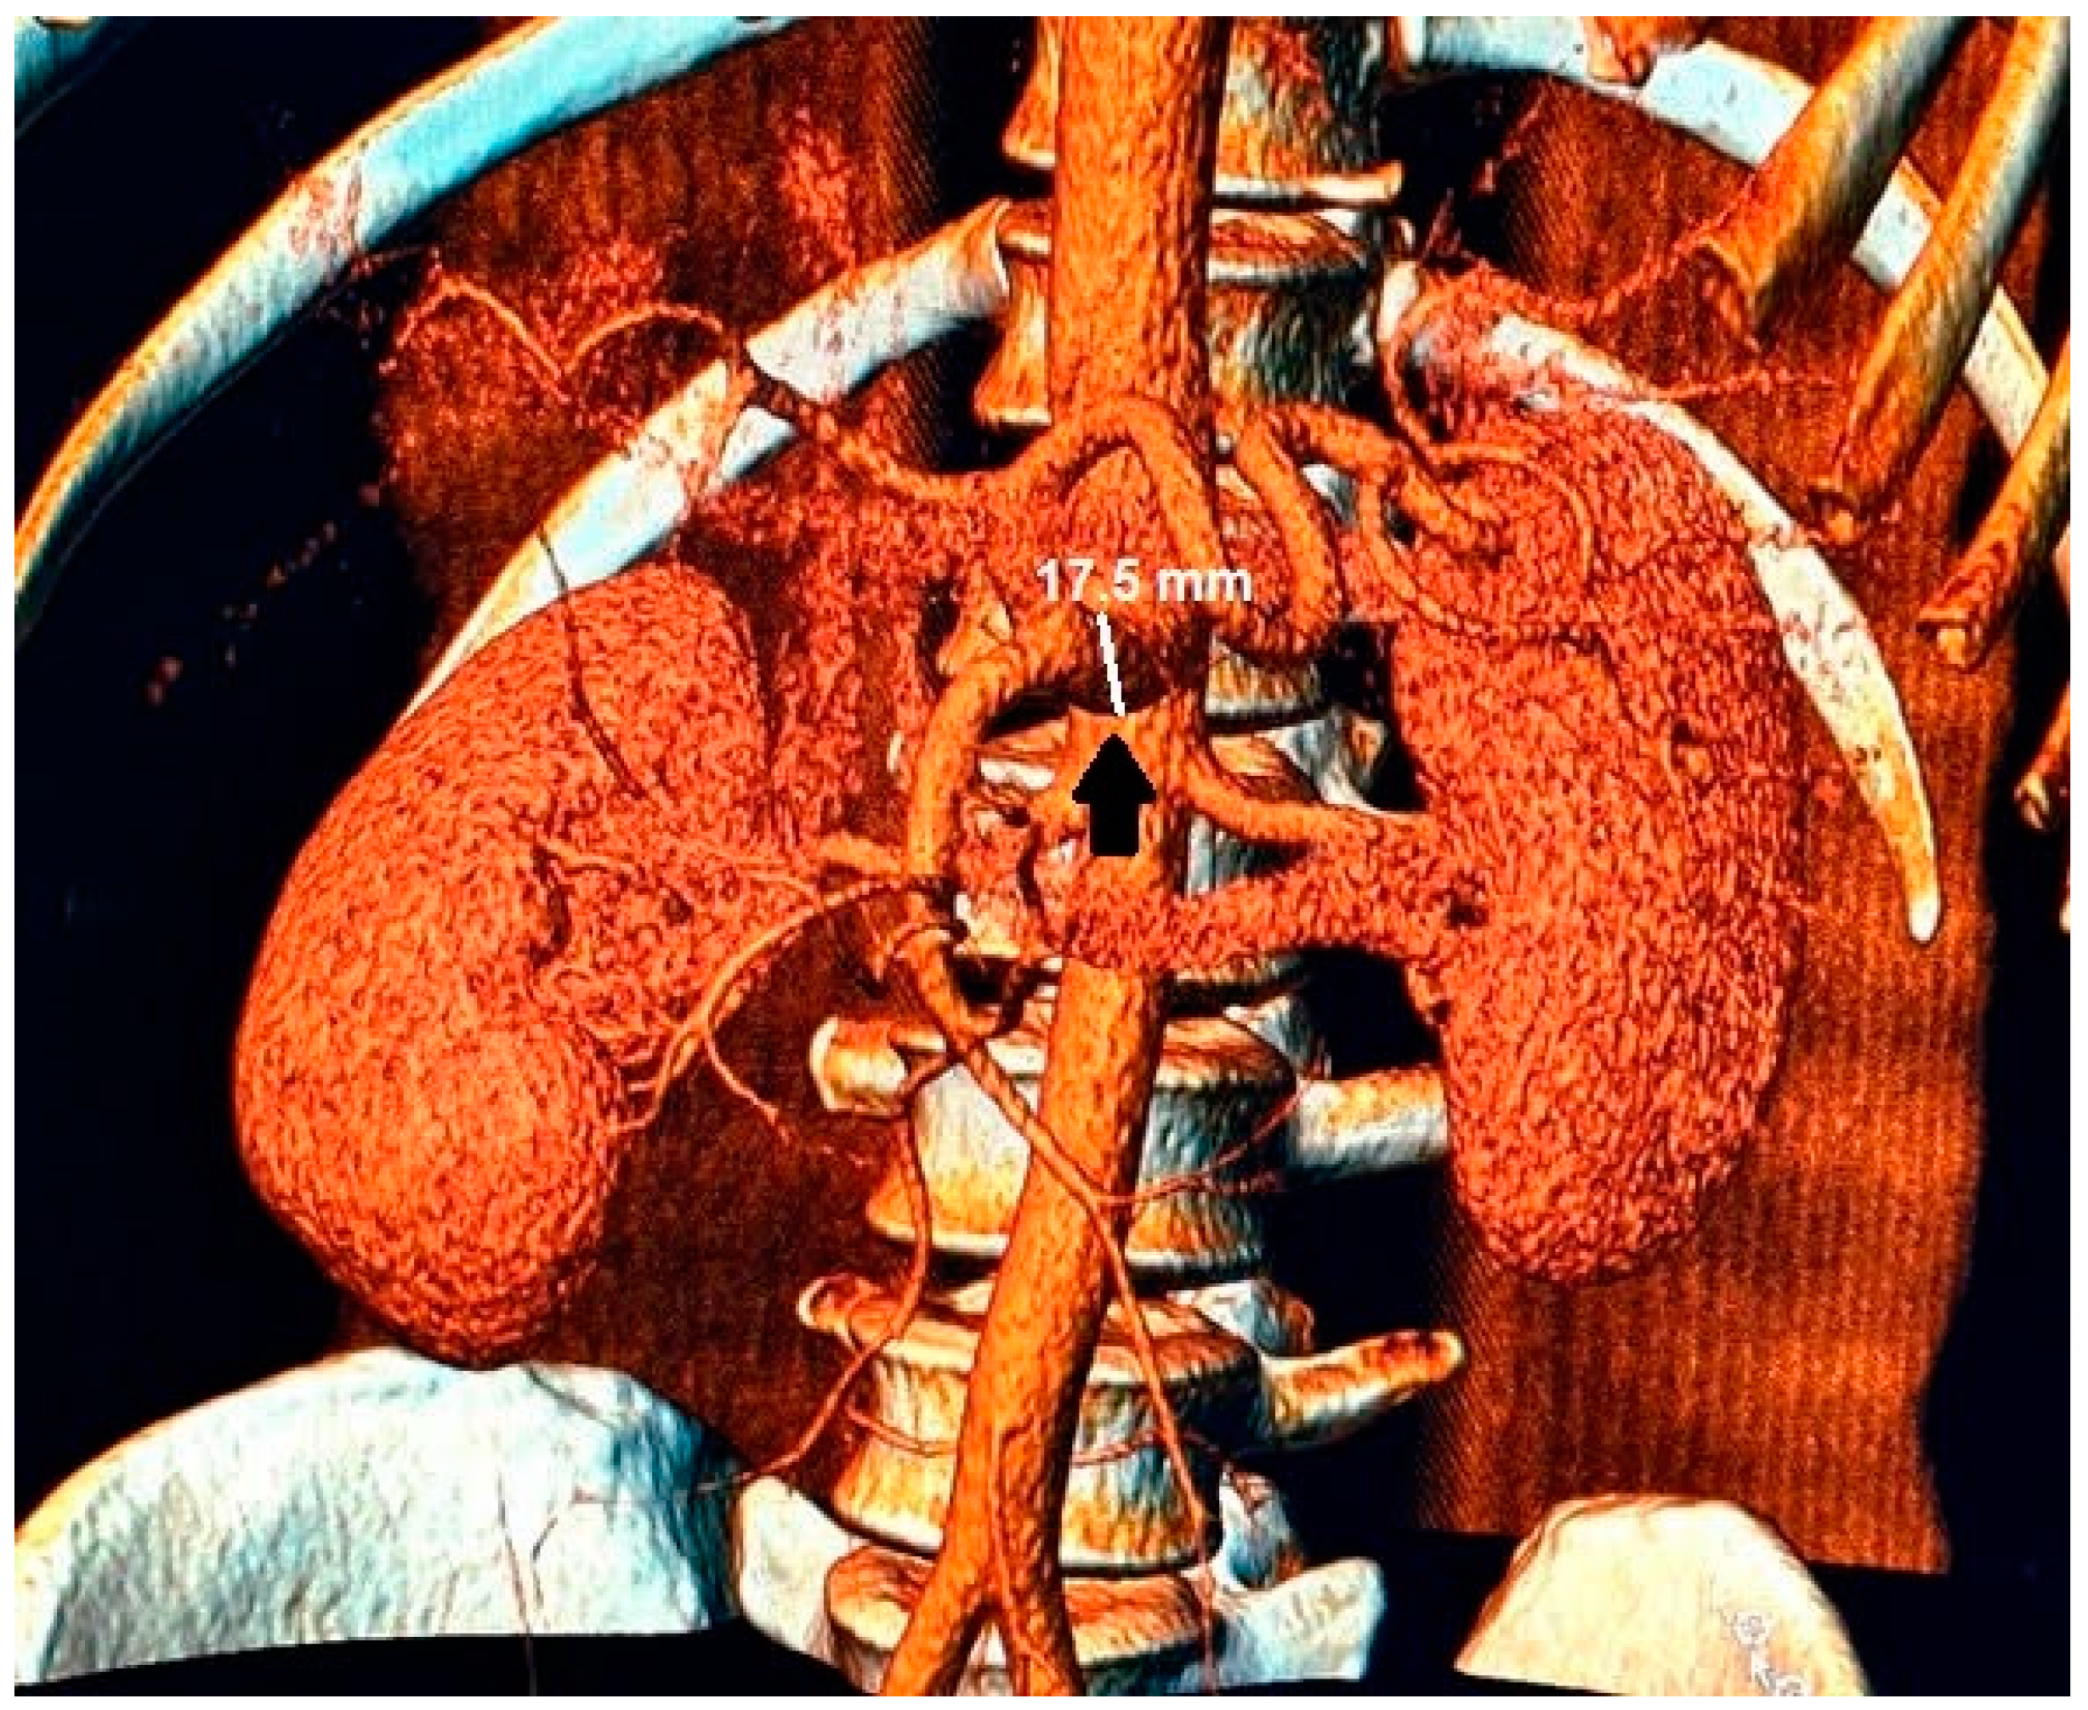

Figure 3.

In the 3D reconstruction of CT scan images, the enlarged celiac-mesenteric trunk can be observed indicated by a black arrow.